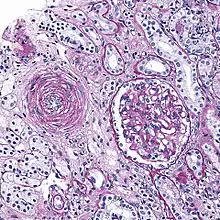

Also arterial hyalinosis and arteriolar hyalinosis refers to thickening of the walls of arterioles by the deposits that appear as homogeneous pink hyaline material in routine staining.[3] It is a type of arteriolosclerosis, which refers to thickening of the arteriolar wall and is part of the aging process.[4]

This is a type of arteriolosclerosis involving a narrowed lumen.[4] The term "onion-skin" is sometimes used to describe this form of blood vessel[8] with thickened concentric smooth muscle cell layer and thickened, duplicated basement membrane. In malignant hypertension these hyperplastic changes are often accompanied by fibrinoid necrosis of the arterial intima and media. These changes are most prominent in the kidney and can lead to ischemia and acute kidney failure.